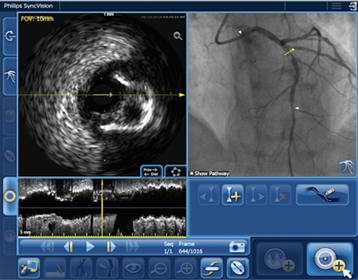

IVUS Co-registration provides easy length measurement with manual IVUS pullback and area/diameter measurements for accurate stent sizing. This feature also provides automated, real-time side-by-side display of co-registered IVUS and angio images to help correlate critical and anatomical landmarks, especially in complex cases, such as bifurcations.1,2,3,4

• Helps you understand precisely where the disease begins and ends directly on the angiogram